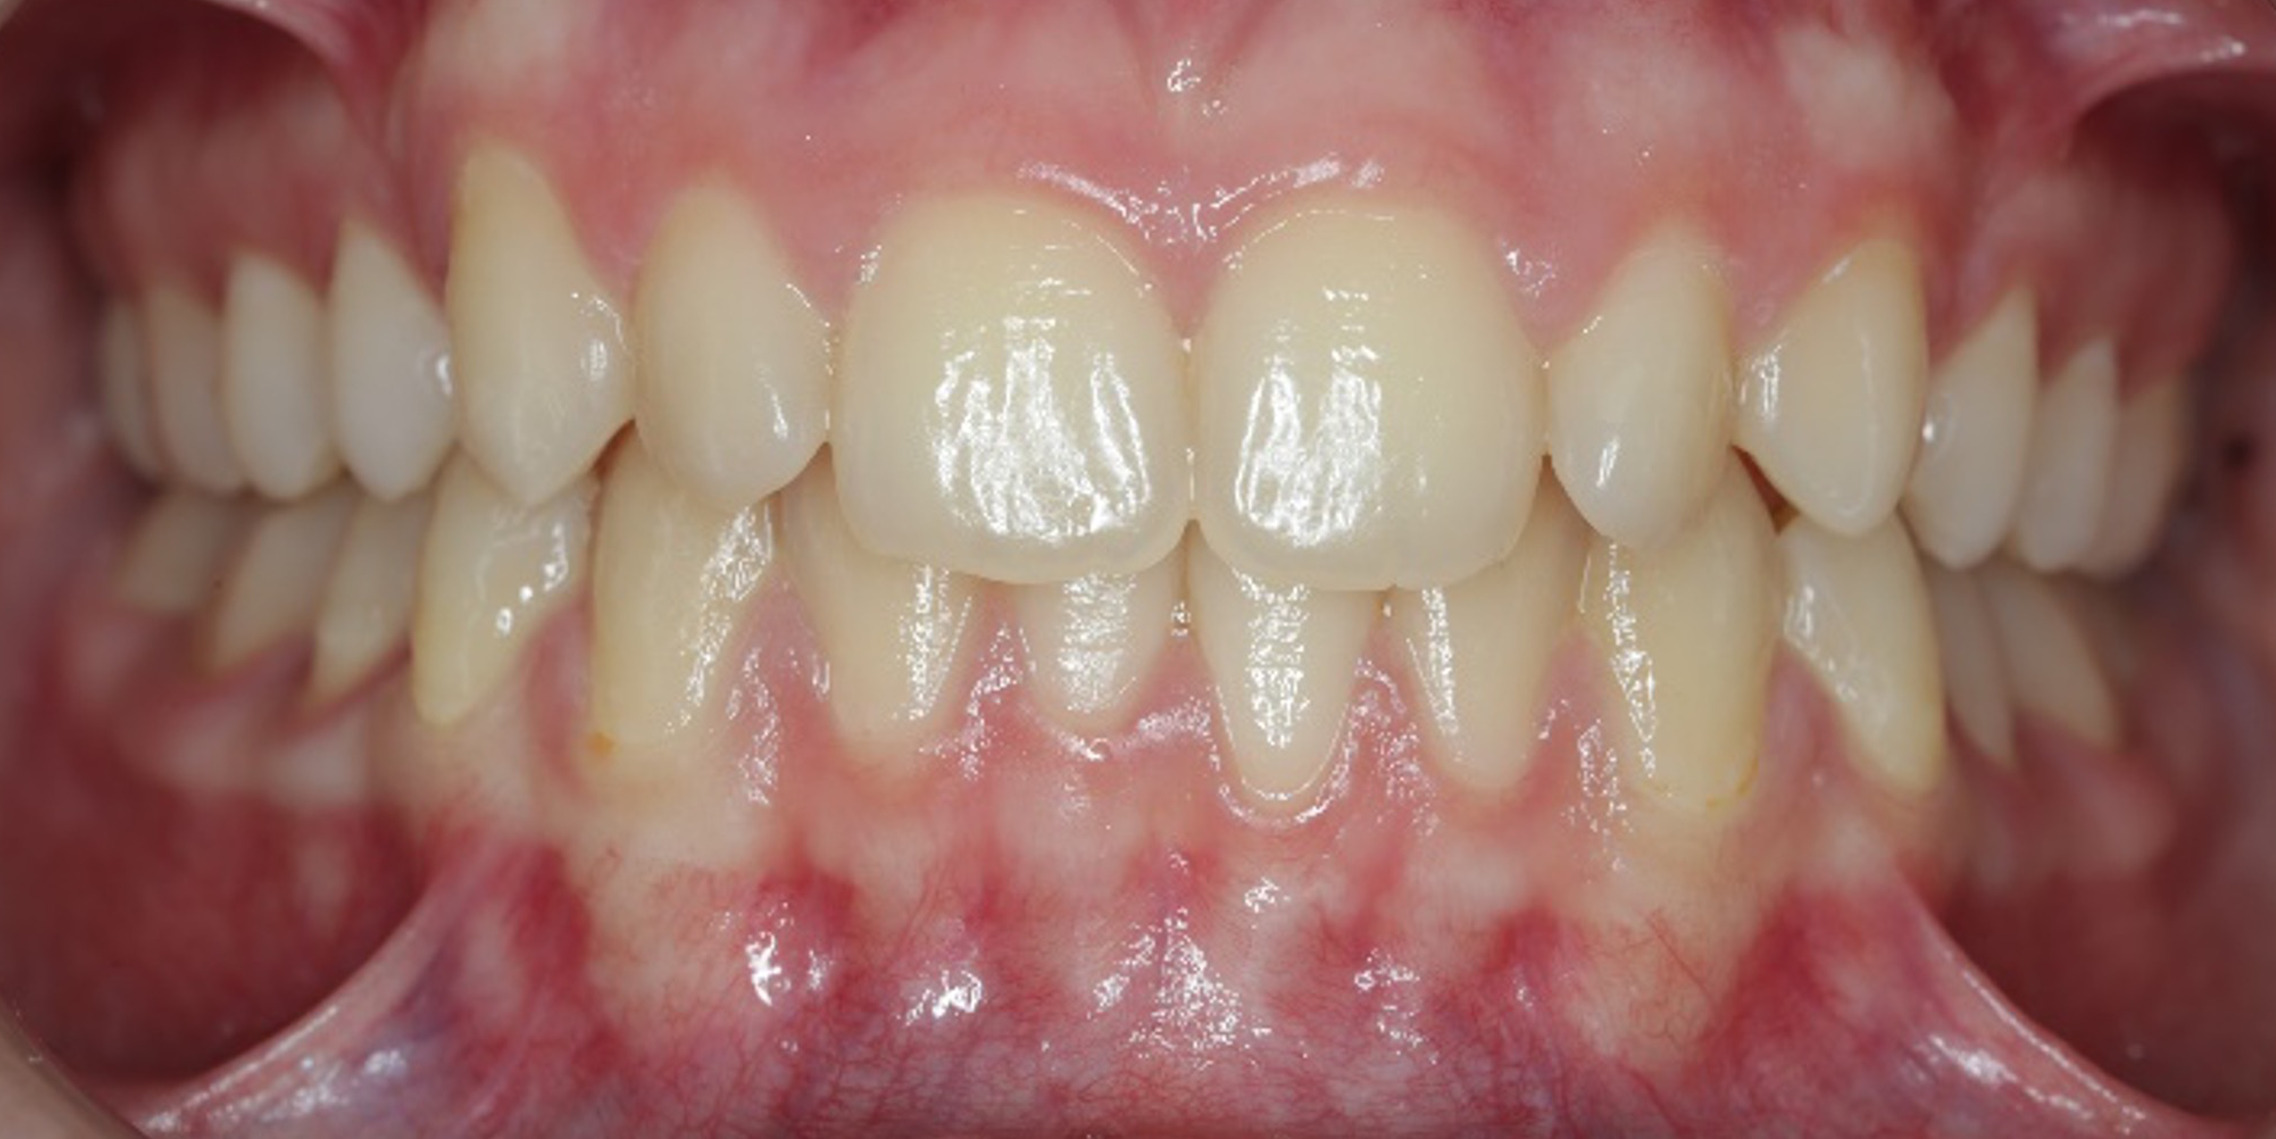

The 14-year-old female patient visited the orthodontic practice in February 2021. The chief complaint was that her upper arch was affecting her confidence in her smile. Upon examination, the patient was found to have a normodivergent facial pattern and a skeletal class II with mandibular retrusion. An intraoral examination revealed narrow arches, a class II molar and canine relationship, deep bite, retroclined upper and lower incisors, and retained teeth 63, 74, and 84.

After undergoing maxillary expansion, Dr. Sorina Blaj assessed the patient again in September 2021, and at that point, tooth 84 had exfoliated, tooth 44 had erupted, and tooth 23 had started to erupt.